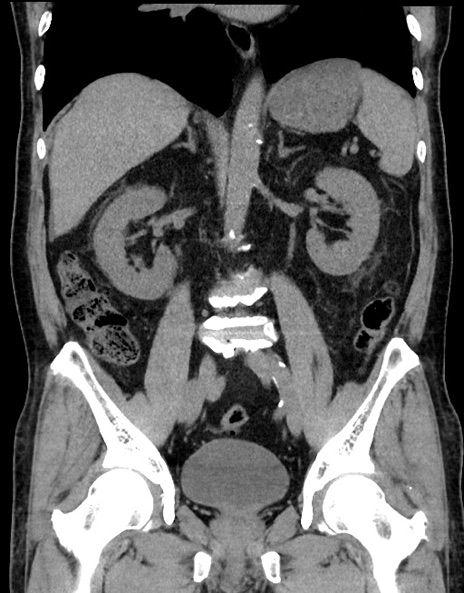

症例15(冠状断像)

【症例】70歳代男性

【主訴】腹痛

【現病歴】今朝から腹痛あり。全体的に痛い。特に左上の方。排ガスが今日はない。冷や汗が出る。

【既往歴】直腸癌術後

【身体所見】左側腹部〜上腹部に圧痛あり。腹膜刺激症状明らかなではない。軽度反跳痛。左下腹部に術後瘢痕あり。

【データ】WBC 7700、CRP 0.02